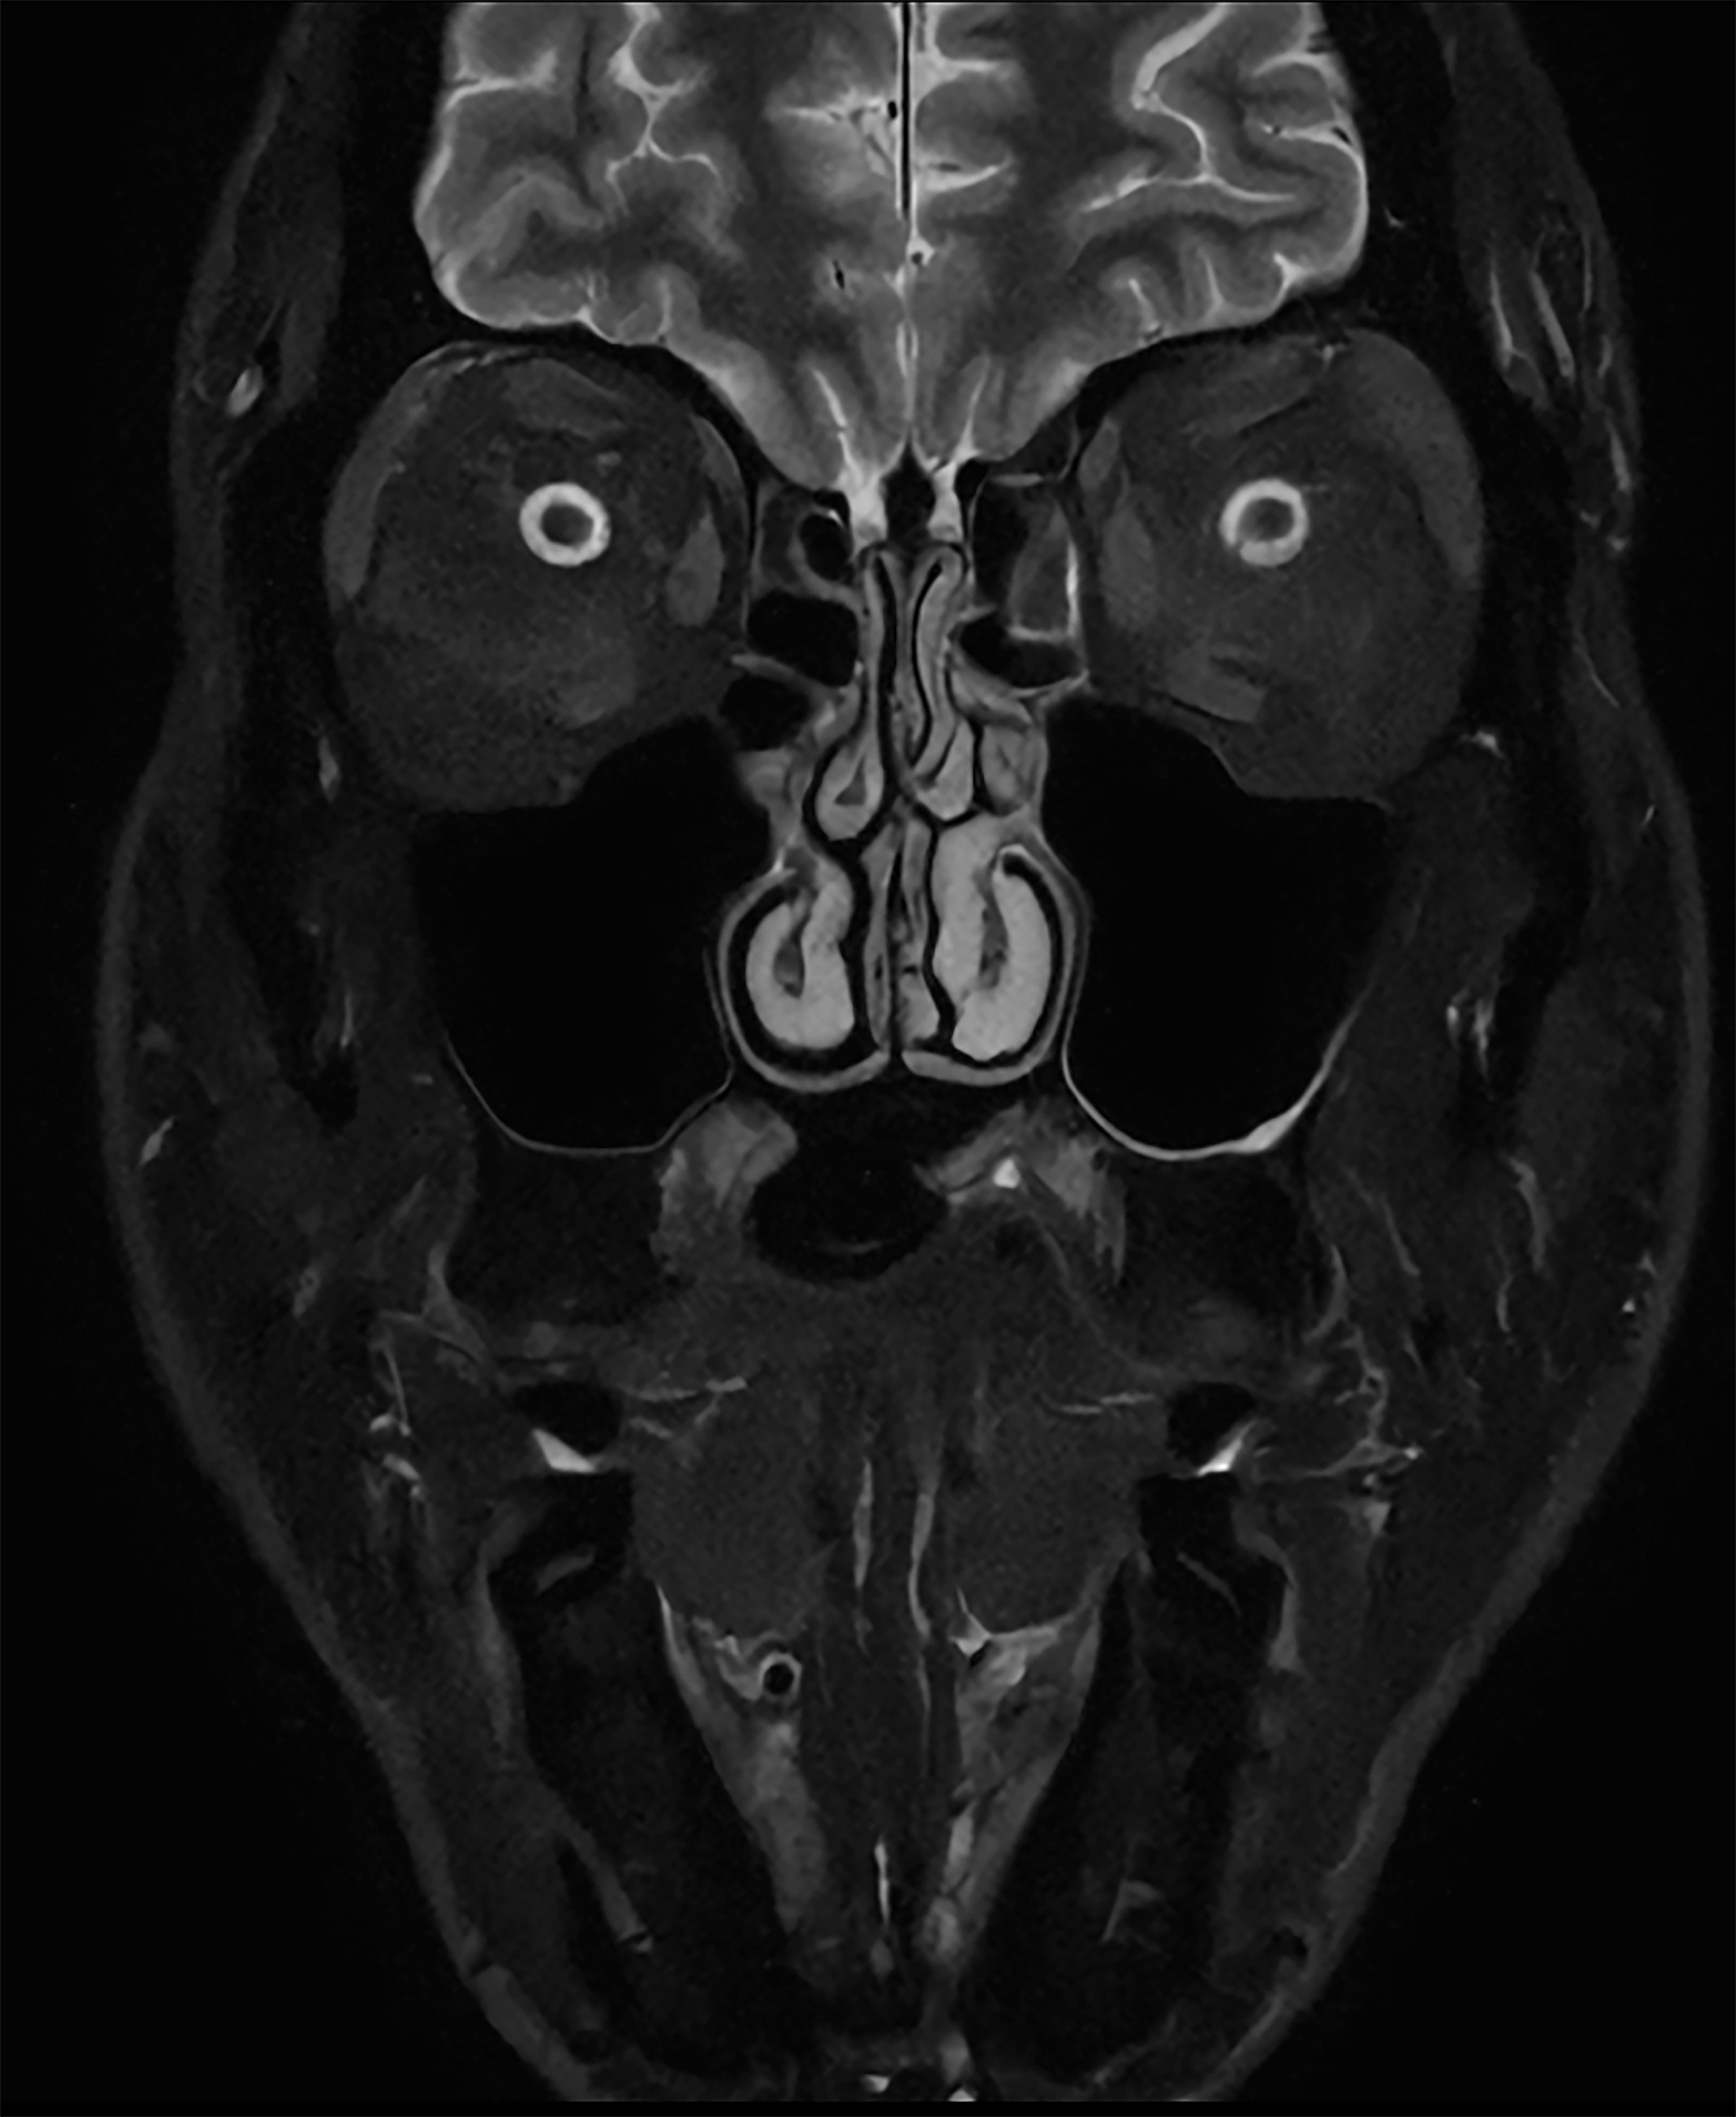

De nieuwste SmartSpeed Precise [1]-technologie verhoogt de productiviteit nog verder, waardoor scans tot drie keer sneller kunnen worden uitgevoerd [7] en de scantijd aanzienlijk wordt verkort terwijl de uitzonderlijke beeldkwaliteit behouden blijft. De kern van SmartSpeed Precise is de dual AI-engine, die zorgt voor een verbetering van 80% in de scherpte van de beelden [8], waardoor de visualisatie wordt verbeterd voor betrouwbaardere en nauwkeurigere diagnoses. Deze krachtige combinatie van snelheid en precisie zorgt ervoor dat radiologen subtiele afwijkingen duidelijker kunnen detecteren, wat uiteindelijk leidt tot betere patiëntresultaten. De nieuwe release van Philips – MR Workspace R12 [6] – introduceert een ‘zero-click’-workflow [9], die het gehele beeldvormingsproces naadloos begeleidt, van het starten van de scan tot het genereren van rapporten. Door handmatige handelingen te verminderen en de efficiëntie te optimaliseren, stelt MR Workspace R12 [6] radiologieafdelingen in staat de patiëntdoorstroming te verbeteren en achterstanden terug te dringen, waarmee tegemoet wordt gekomen aan de toenemende vraag naar snellere en nauwkeurigere beeldvorming. Een belangrijke innovatie binnen MR Workspace R12 [6] is de door AI aangestuurde SmartExam-functie, die 80% van de MR-procedures automatiseert [10], door werkzaamheden te stroomlijnen en beeldvormingsworkflows te standaardiseren.

Andere baanbrekende innovaties zijn onder andere Smart Reading [4], de eerste oplossing in de industrie die cloudgebaseerde, door AI aangestuurde kwantitatieve rapportage naadloos [11] integreert. Smart Reading maakt gebruik van geavanceerde AI-platformen zoals icobrain (icometrix) voor neurologie – inclusief detectie van de ziekte van Alzheimer – en QP-Prostate (Quibim) voor geavanceerde diagnose van prostaatkanker. Door objectieve, zeer betrouwbare diagnoses te leveren, maken deze zero-click AI-oplossingen [9] gestroomlijnde, op data gebaseerde besluitvorming mogelijk voor artsen. Met MR Workspace R12 [6], SmartSpeed Precise [1] en Smart Reading [4] blijft Philips de grenzen van AI in MRI verleggen om de efficiëntie, nauwkeurigheid en toegankelijkheid van diagnostische beeldvorming te vergroten en tegelijkertijd de weg vrij te maken voor de toekomst van autonome MR-scanning.